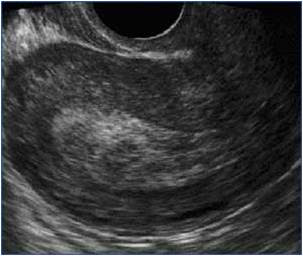

| Anembryonic miscarriage with evidence of

a collapsed sac with diameter more than 20 mm and no evidence of fetal pole or

yolk sac. |